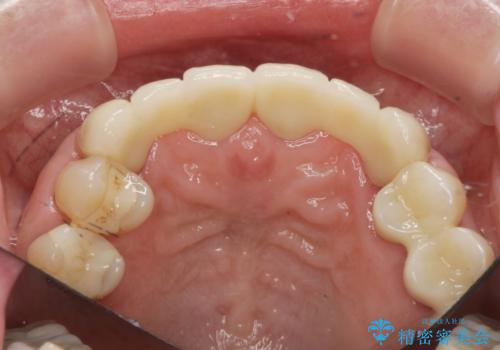

不自然な前歯ブリッジ ジルコニアブリッジによるやり替え

- 20年前に入れたブリッジの見た目の改善を求めて来院されました。

丁寧に現在装着されているブリッジを除去後、精度の高いジルコニアブリッジで審美性の改善を計画します。

前歯に限らず拡大鏡を用いた精密な形成・シリコンを用いた精度の高い印象を徹底することで治療全体の質を高め、審美性だけでなく長期的な予後を期待することができます。